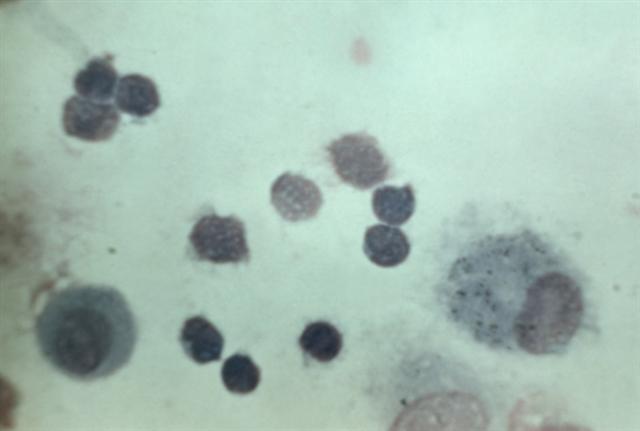

Рис. 5. Микропрепарат бронхоальвеолярного смыва больного саркоидозом легких в активной фазе: в составе клеток преобладают лимфоциты (указаны стрелками).